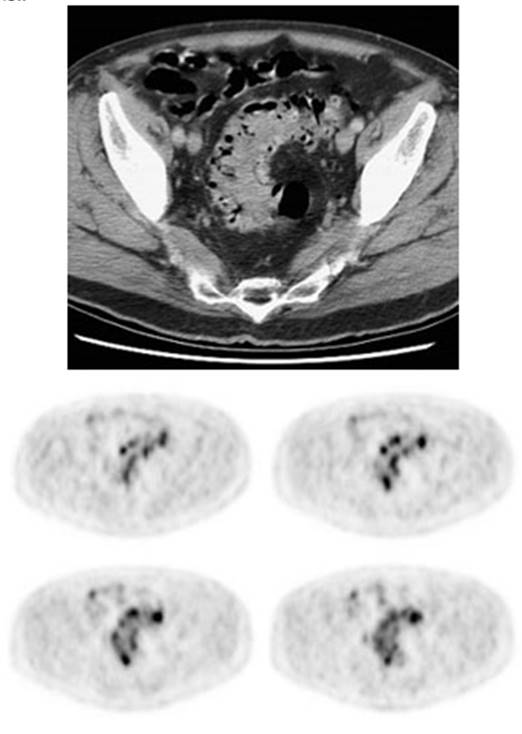

Figure 5 - Genitourinary activity: The image below demonstrates normal

Figure 6 - Genitourinary activity: The image below

demonstrates activity within the collecting system of a transplanted kidney

(black arrows). This should not be mistaken for an abnormality.

Figure 7 - Bladder cancer: Despite urinary excretion

of the radiotracer, this patients bladder cancer

(white arrows) is readily identified on the PET scan (black arrows). In

general, however, urinary excretion of FDG limits evaluation of urinary tract

malignancy